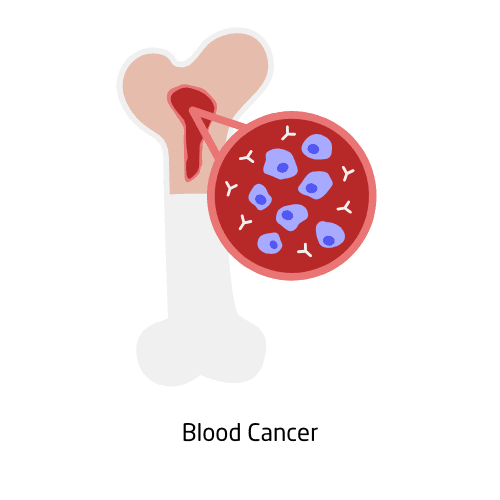

Blood cancers include leukemia, lymphoma, and multiple myeloma, all of which affect the blood, bone marrow, or lymphatic system. These cancers can disrupt normal blood cell production and weaken the immune system. Symptoms vary but often include fatigue, frequent infections, unexplained weight loss, or swollen lymph nodes. Diagnosis usually requires blood tests, biopsies, or imaging.

Treatment may involve chemotherapy, targeted therapy, immunotherapy, or stem cell transplants. Support from hematology specialists, mental health professionals, and peer groups is vital. Advances in research continue to improve survival and quality of life.